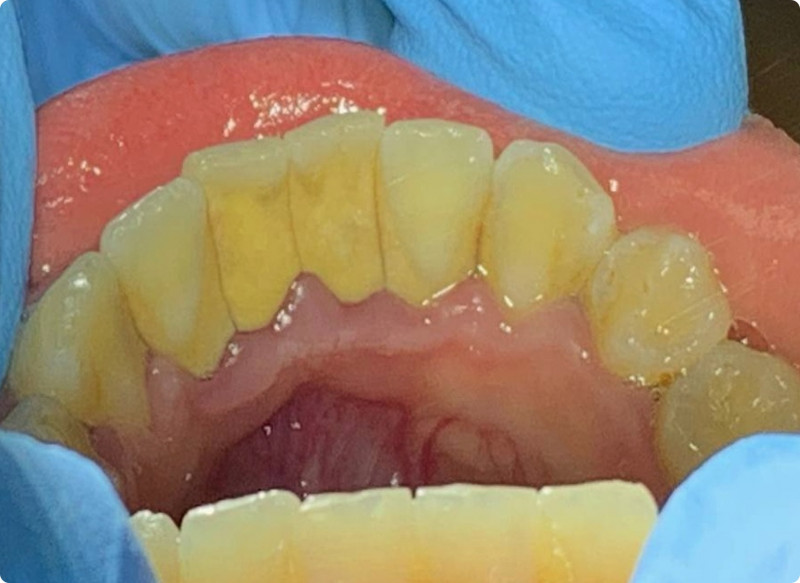

Чистка зубов Air-flow

Доктор: Трингорт Станислав Альбертович

Комплексная чистка зубов в 4 этапа: Ультразвуковая обработка, Air Flow, полировка с щеткой и пастой, капа с реминерализирующим гелем. Врач Трингорт С.А.